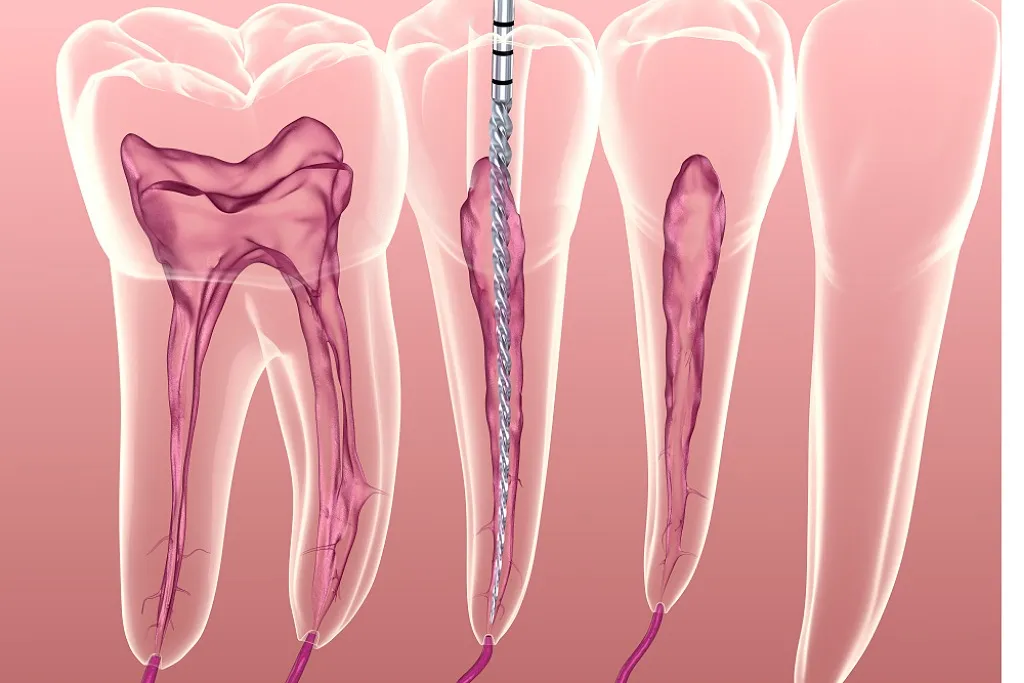

زمانی که پالپ (بخش داخلی دندان شامل عصب و رگهای خونی) دچار التهاب یا عفونت میشود، نیاز به درمان ریشه وجود دارد. این وضعیت معمولاً به علت پوسیدگیهای عمیق، ترکخوردگی دندان، ضربه شدید یا درمانهای دندانی متعدد اتفاق میافتد. در عصبکشی، پالپ آسیبدیده تخلیه، کانالهای ریشه پاکسازی، ضدعفونی و در نهایت با مواد مخصوص پر و مهر و موم میشود.

- معاینه و تشخیص: معاینه بالینی و تصویربرداری دیجیتال برای ارزیابی وضعیت ریشه و پالپ.

- باز کردن دندان: سوراخکردن سطح دندان برای دسترسی به کانال ریشه.

- تخلیه پالپ: برداشتن بافت عفونی یا آسیبدیده با ابزارهای دقیق.

- ضدعفونی کانال: شستوشو با مواد ضدباکتری و شکلدهی کانالها.

- پرکردن کانال: پر کردن ریشه با گوتاپرکا یا مواد مشابه برای جلوگیری از ورود باکتری.